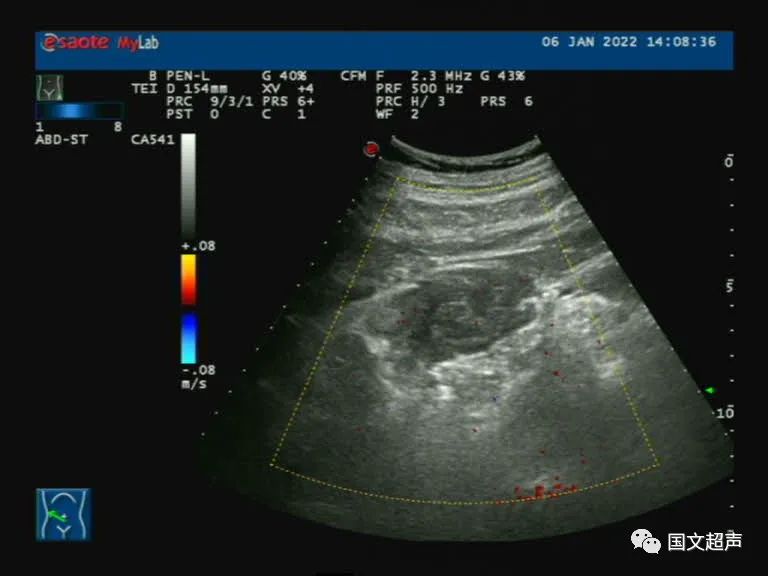

病例2:患者范某,男,47歲,雙腎功能不全,透析,自述突發(fā)右側腰腹部鈍痛3天,疼痛前曾劇烈咳嗽。

超聲檢查:右側髂肌、髂腰肌淺層及前方探及不均質低回聲,形態(tài)不規(guī)則,邊界不清晰,CDFI:血流信號不明顯,向后方延伸至腰方肌及腰大肌之間,周圍網(wǎng)膜及脂肪組織增厚。結合增強CT檢查結果,考慮血腫,臨床觀察對癥治療。